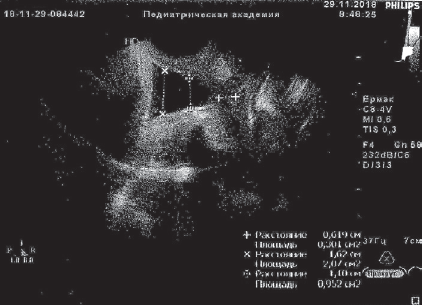

Получала сохраняющую беременность терапию с подключением трех сеансов мембранного плазмафереза (МПА) с возвратом гепаринкриомодифицированной аутоплазмы (при двух МПА по 200 мл), 12 сеансов ФК ультрафиолетовыми (№ 6) и лазерными (№ 6) лучами, без осложнений. После курса лечения анализы крови нормализовались, по данным УЗИ картина улучшилась, появилась сохранная часть шейки матки 6 мм, вероятно, за счет снижения внутриматочного давления в каудальном направлении. Пролабирования плодного пузыря за пределы наружного зева не визуализировалось в зеркалах и при УЗИ (рис. 1, 2).

Рис. 2. Данные ультразвукового исследования пациентки Ч., 33 недели беременности, после курса эфферентной терапии, динамика положительная

Fig. 2. Ultrasonic examination of patient Ch., 33 weeks of gestation, after efferent therapy course — positive results